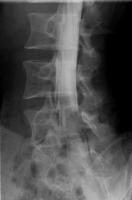

全脊椎撮影

脊椎全体の配列を観察する検査です。

自然位で寝た状態から、体を左右に曲げた側屈位や、腕と脚を引っ張った伸展矯正位、背中を反らせた最大後屈位などを撮影します。

EOS検査の立位荷重位と比較することが可能です。